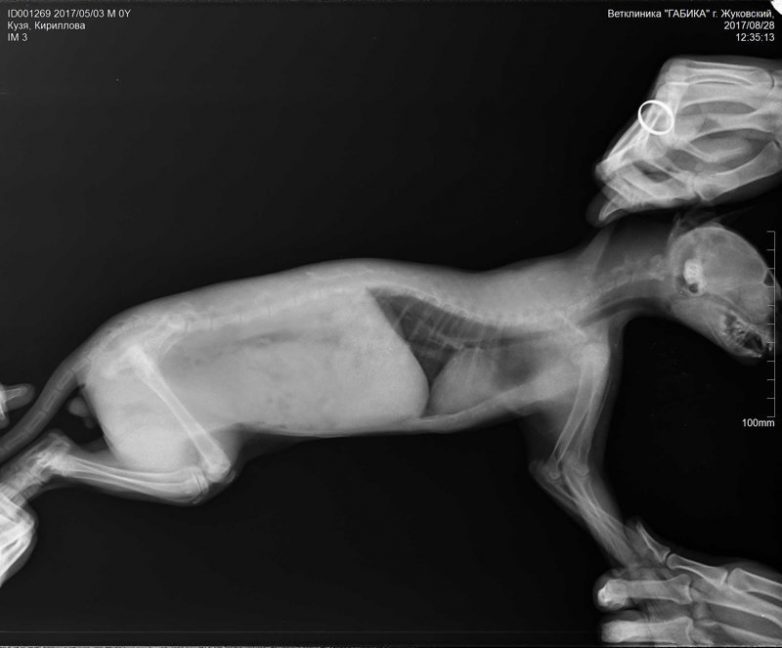

Такой шустряк- за кошкой бегал- влез на лазалку для кошки (и как смог то??) и загремел с нее на пол с высоты 2 метра. Отбил видно внутренности себе и косточки повредил. Ходить не мог недели две, орал и перемещался перекатыванием. Возили к врачам, рентген и все такое (какая же это маета). Такой малюха, что на рентгене (снимки ниже) толком ничего и не увидели врачи, но сказали что от недостатка питания косточки очень слабые- надо кальция ему побольше давать. Лечили, он постепенно оклемался, но видно несколько поврежден был то ли позвоночник, то ли таз. Сейчас ходит с немного вывернутыми наружу задними ножками, как балерина и задницу к низу пригибает (ну прямо как овчарка немецкая). Толком не может прыгнуть, но смотрим- постепенно тренируется, на стул уже с разгона залетает, с места пока ни как-только на когтях. Но все равно уже стал членом семьи, может когда и ножки исправятся надеемся. Сейчас ему пол года. На лазалку все равно лазит, не боится. Вот такая краткая история появления у нас друга Кузьки. Фотоотчет прилагаю: